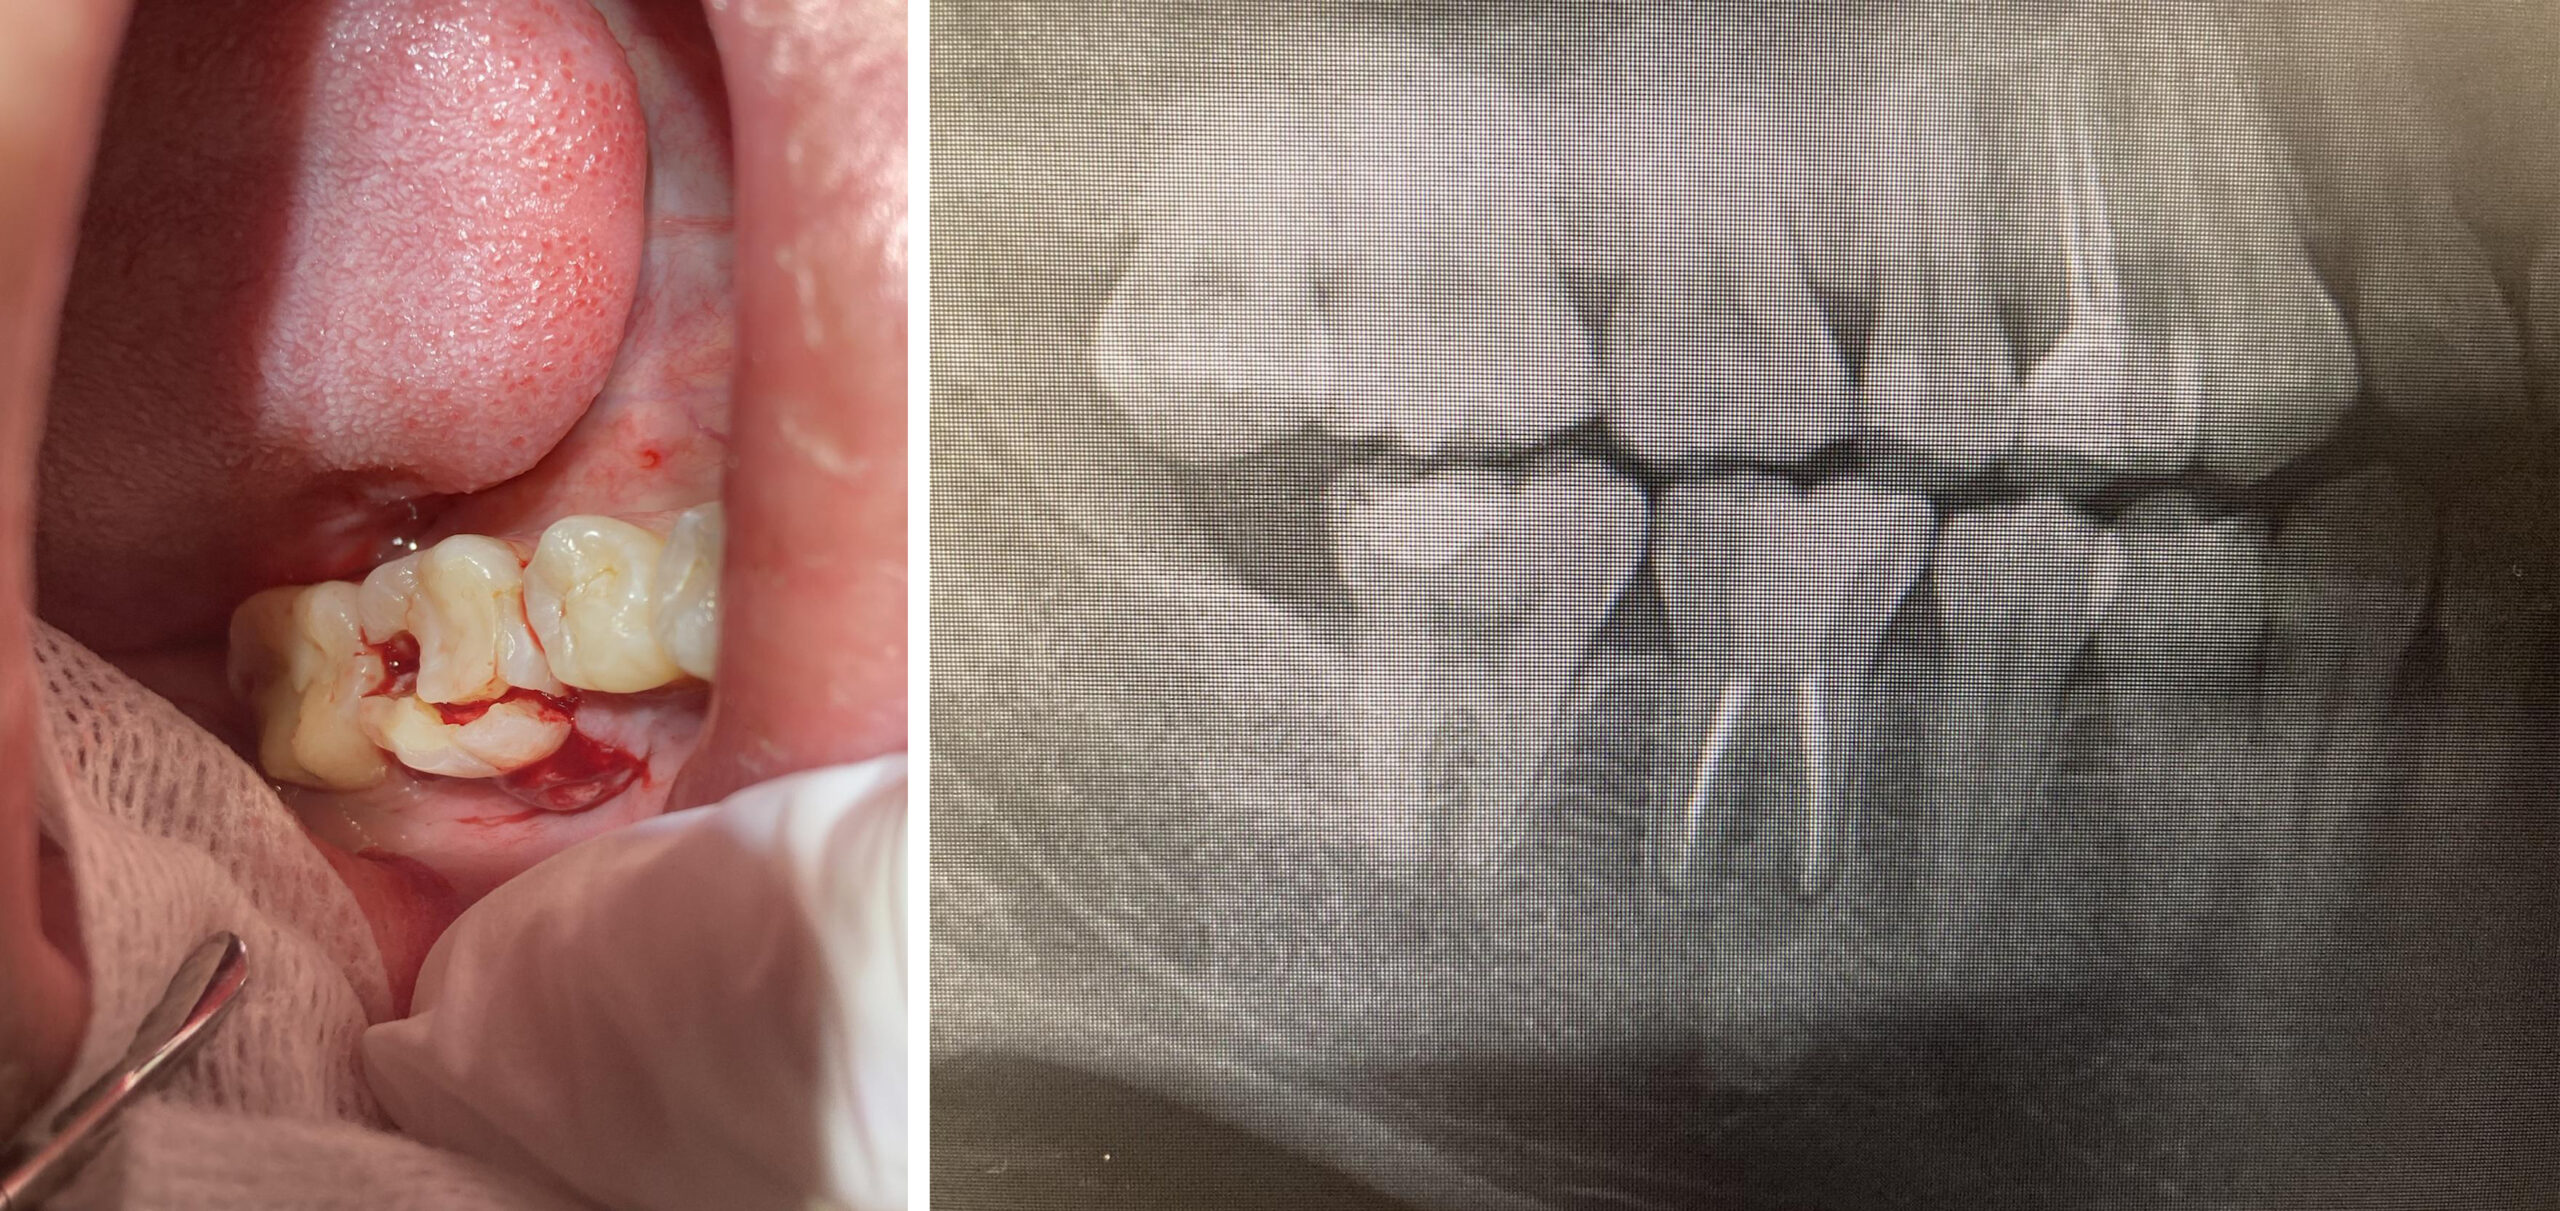

顎水平埋伏智歯